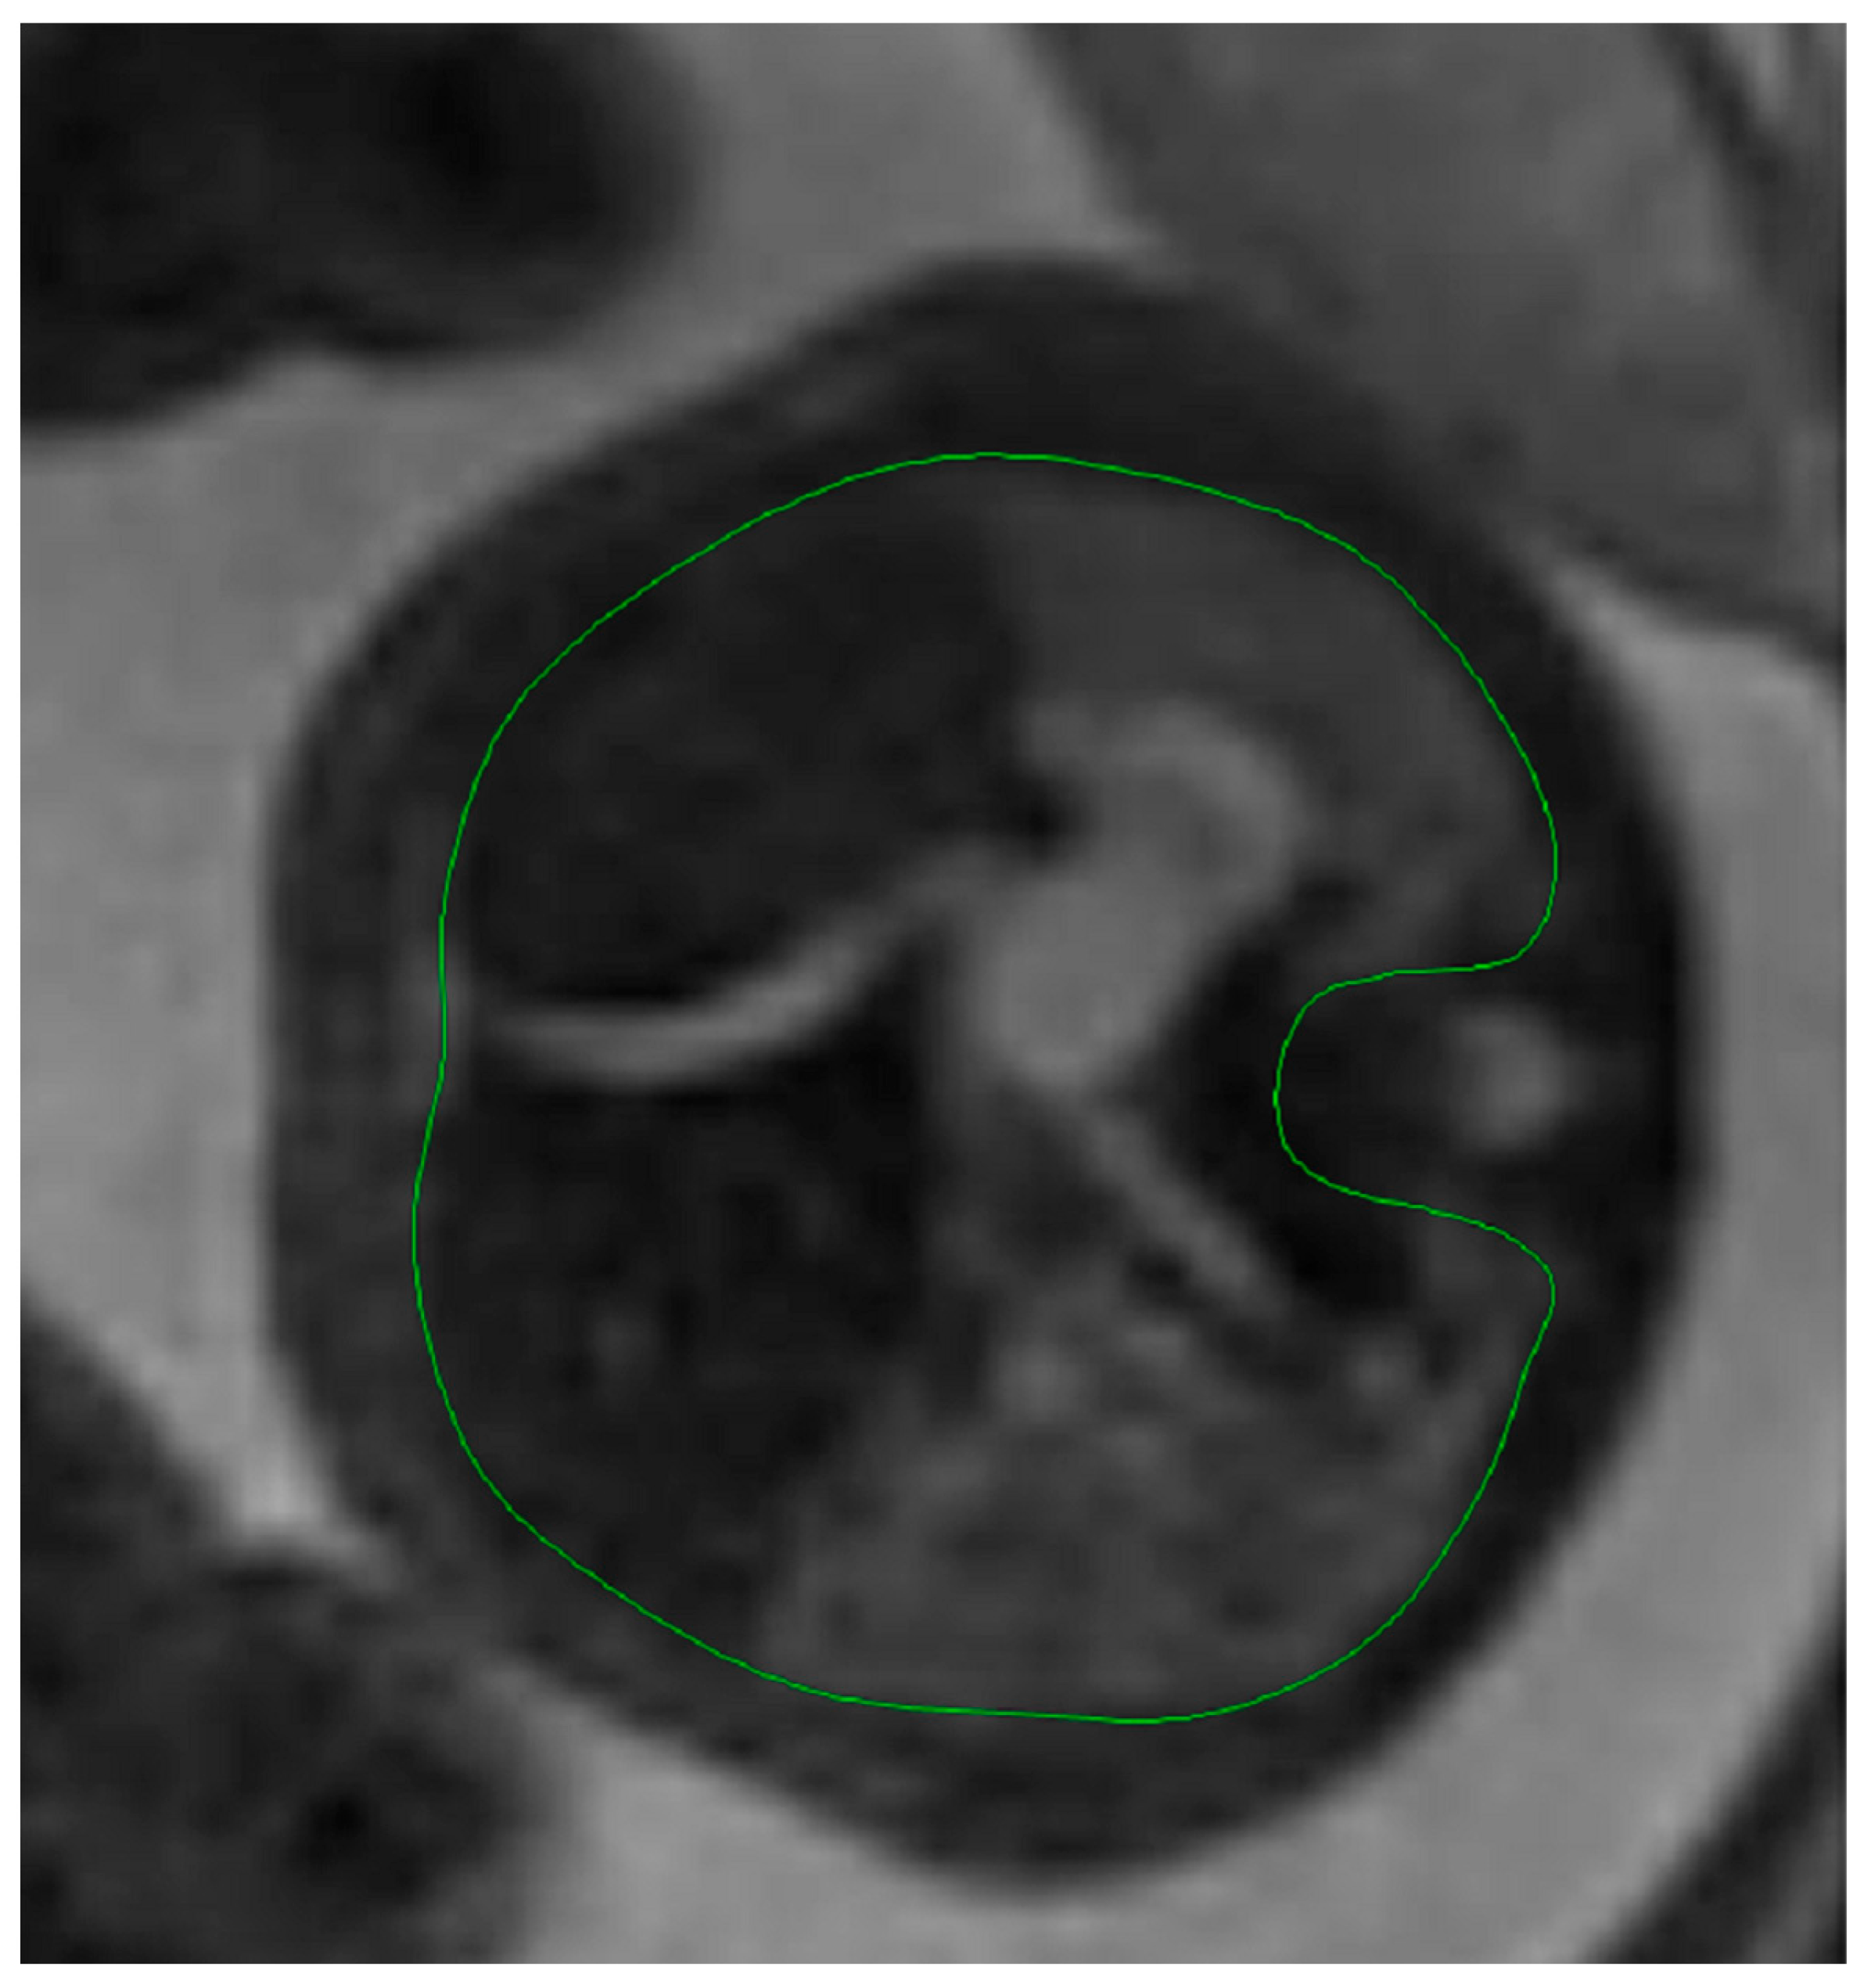

Fetal lung volume was calculated by using a new method to reduce the overestimation of the lung volume. The first step was tracing the lung area of both lungs on each slice. We then obtained the mean between every 2 consecutive slices and multiplied the value by the distance between them. Finally, we calculated the sum of all these values and obtained the TLV for each lung. For easier viewing of this parameter, we calculated the total lung volume ratio (TLVR) by calculating the ratio between our observed value and the expected lung volume values obtained from reference articles that measured standard values for lung volumetry using MRI. To be more precise, we looked at the studies of Meyers et al., Rypens et al., Osada et al., and Sefidbakht et al. [16,17,18,19] and calculated a mean from them that was used as our reference. Figure 1 and Figure 2.

Figure 2. Ultrasound axial four-chamber image of the fetus showing the tracing method for calculating the LHR, using the RadiAnt DICOM Viewer program, version number 2022.1.1. The green line represents the lug area on the nonherniated side.